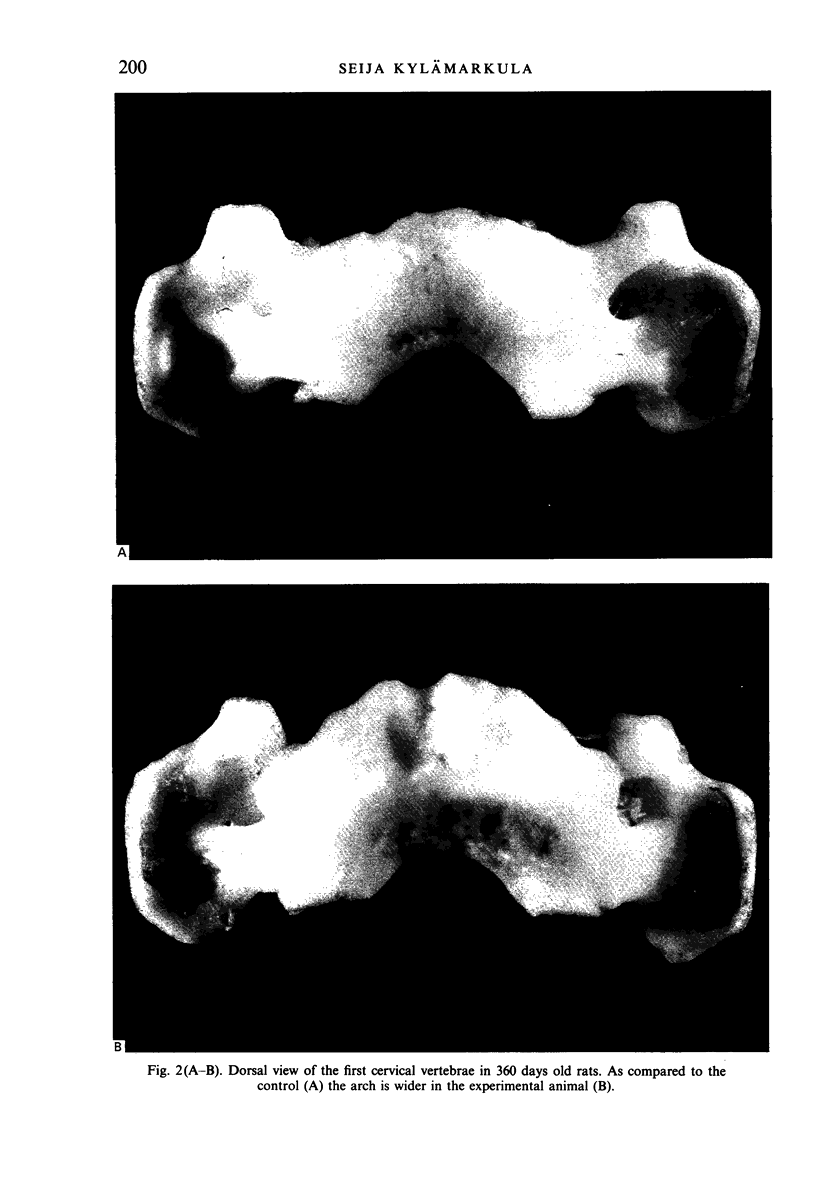

The influence of altered neck muscle function on the morphology of the craniocervical area was studied in the rat. The neck muscles were detached from their cranial attachments at 14 days of age and the skulls subjected to macroscopic, radiological and microscopic examination at 180, 360 and 450 days of age. Visual observations only were made on the three upper cervical vertebrae. As compared with the situation in the unoperated control animals, the occipital area of the experimental skull was flattened, the superior margin of the foramen magnum was irregularly curved, the sutural serration appeared less accentuated in the posterior lambdoid suture, the normally smooth curvature of which had a caudal flexture in the middle. The spheno-occipital synchondrosis was structurally similar to that in the controls, and no obliteration was seen. The angular relations between the basicranial components changed following the operation in that the posterior basicranial components at first were bent downwards while the situation was later reversed. To compensate for the upward inclination of the posterior part of the basi-occipital bone, the anterior rim of the foramen magnum had become reshaped. The downward flexion of the basicranium was considered to be the result of the decreased nuchal muscle tension whereas the reversed angle phenomenon was possibly brought about by tissue scarring. The dorsal arch of the first cervical vertebra was wider craniocaudally than in the controls and its cranial border was bent ventrally. The second vertebra differed from the controls in that the spinous process was longer and in some cases was directed upwards.(ABSTRACT TRUNCATED AT 250 WORDS)